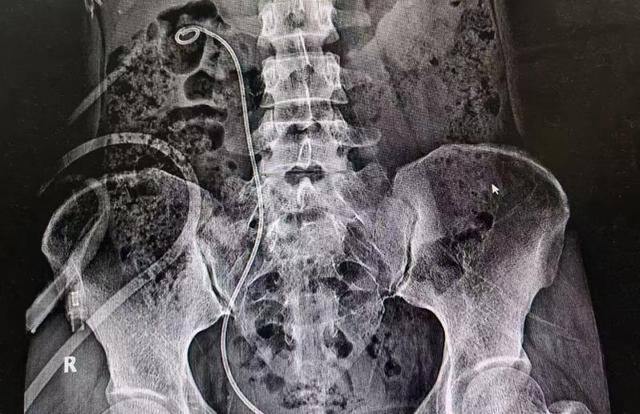

术后,闵女士接受了抗感染、补液等治疗,恢复状况良好。很快,她便可以下床活动,身体各项指标也逐步恢复正常。术后复查腹部卧位平片显示左侧肾结石已被清除干净。

(术后影像:未见结石)